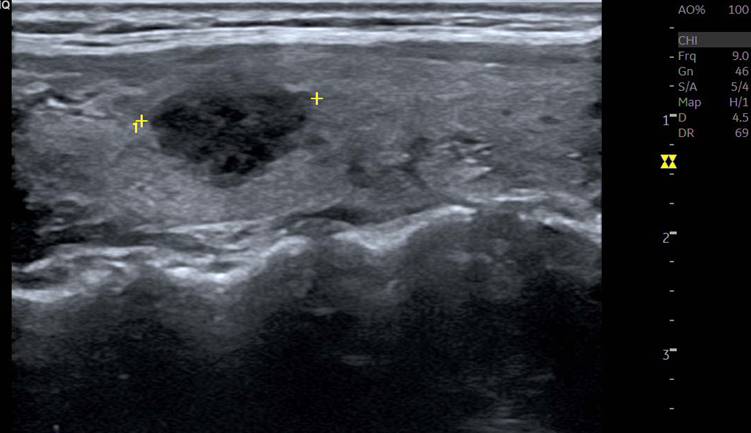

[360,] 64/F,Right anterior neck pain

다음 환자의 진단은?

Medullary thyroid carcinoma

Nodular hyperplasia

papillary thyroid carcinoma

follicular adenoma

Subacute thyroiditis